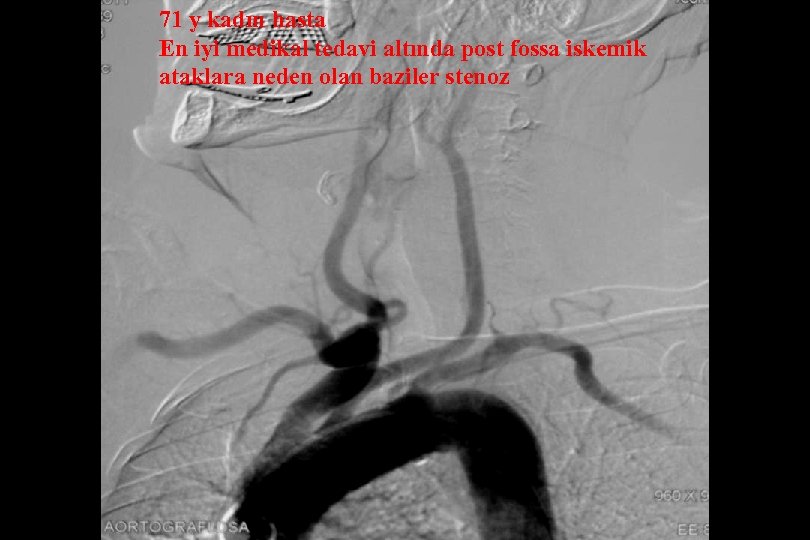

71 y kadın hasta En iyi medikal tedavi altında post fossa iskemik ataklara neden olan baziler stenoz

Sağ brakial yaklaşım ile Reflex /Navien servikal R- VA’e ve intrakraniyal segmente ilerletilmiştir.

PTA sonrası

. . 6 mm Solitaire ile Stentleme sonrası